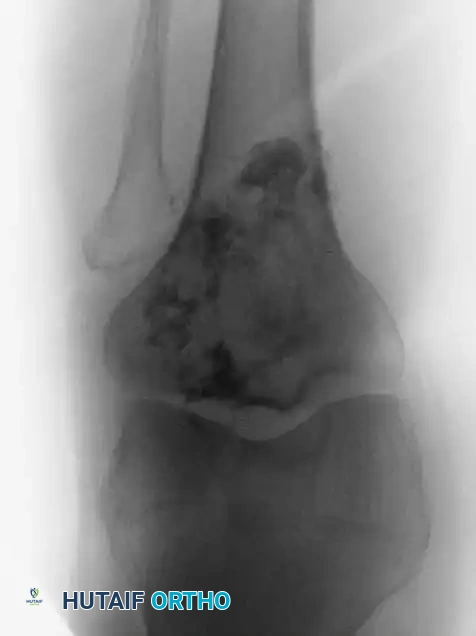

Image

Fig. 22-6 A and B: Anteroposterior and lateral radiographs demonstrating a secondary chondrosarcoma arising from a preexisting osteochondroma in a 67-year-old woman. Note the massive, irregular cartilaginous cap.

Surgical Warning: The size of the cartilaginous cap of an osteochondroma is a critical metric. Evaluated via MRI or CT, a cartilaginous cap thicker than 2 cm in a skeletally mature patient is highly suspicious for secondary chondrosarcoma and warrants immediate biopsy or wide resection.